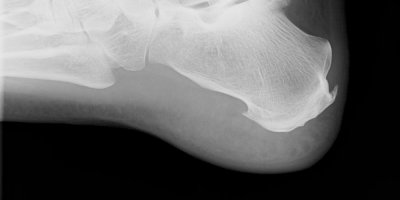

Rentgen patní ostruhy FYZIOklinika